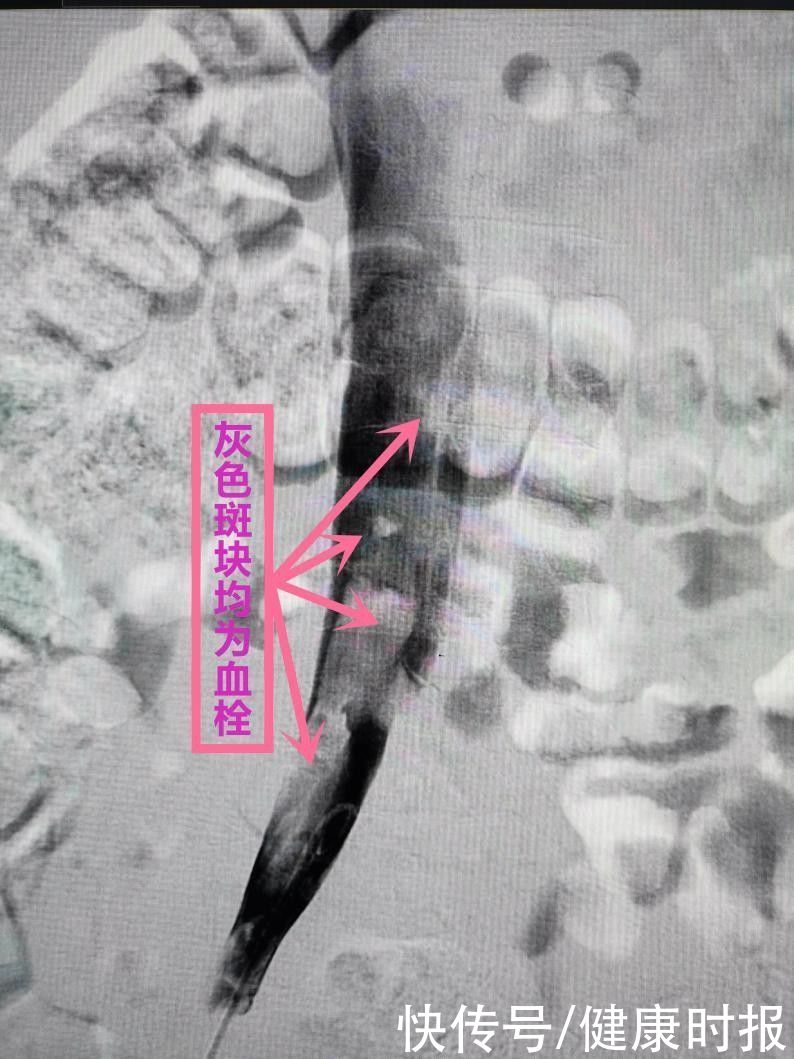

血管内灰色区域全是大块血栓。 受访者供图

“当时他的左腿已经是右腿的两倍粗,经血管造影后发现,左下肢主静脉几乎全部被血栓堵塞。而且在小谢进行下肢及下腹部CTV检查时还在右下肢主静脉起始部和左右下肢主静脉交汇处的下腔静脉,发现了大块的血栓形成。”李晟告诉健康时报采访人员,血栓大面积爆发与其玩电脑久坐不起身有关。如果不及时治疗,小谢的双下肢静脉都将被血栓塞满,最终导致双腿瘫痪,严重时血栓脱落引起肺栓塞,将危及生命。后来,